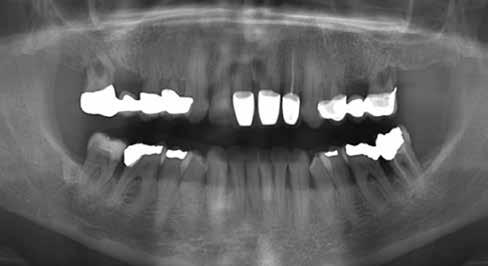

20–22. ábra: 2017-es, 2019-es és 2022-es panorámaröntgen-felvételek.